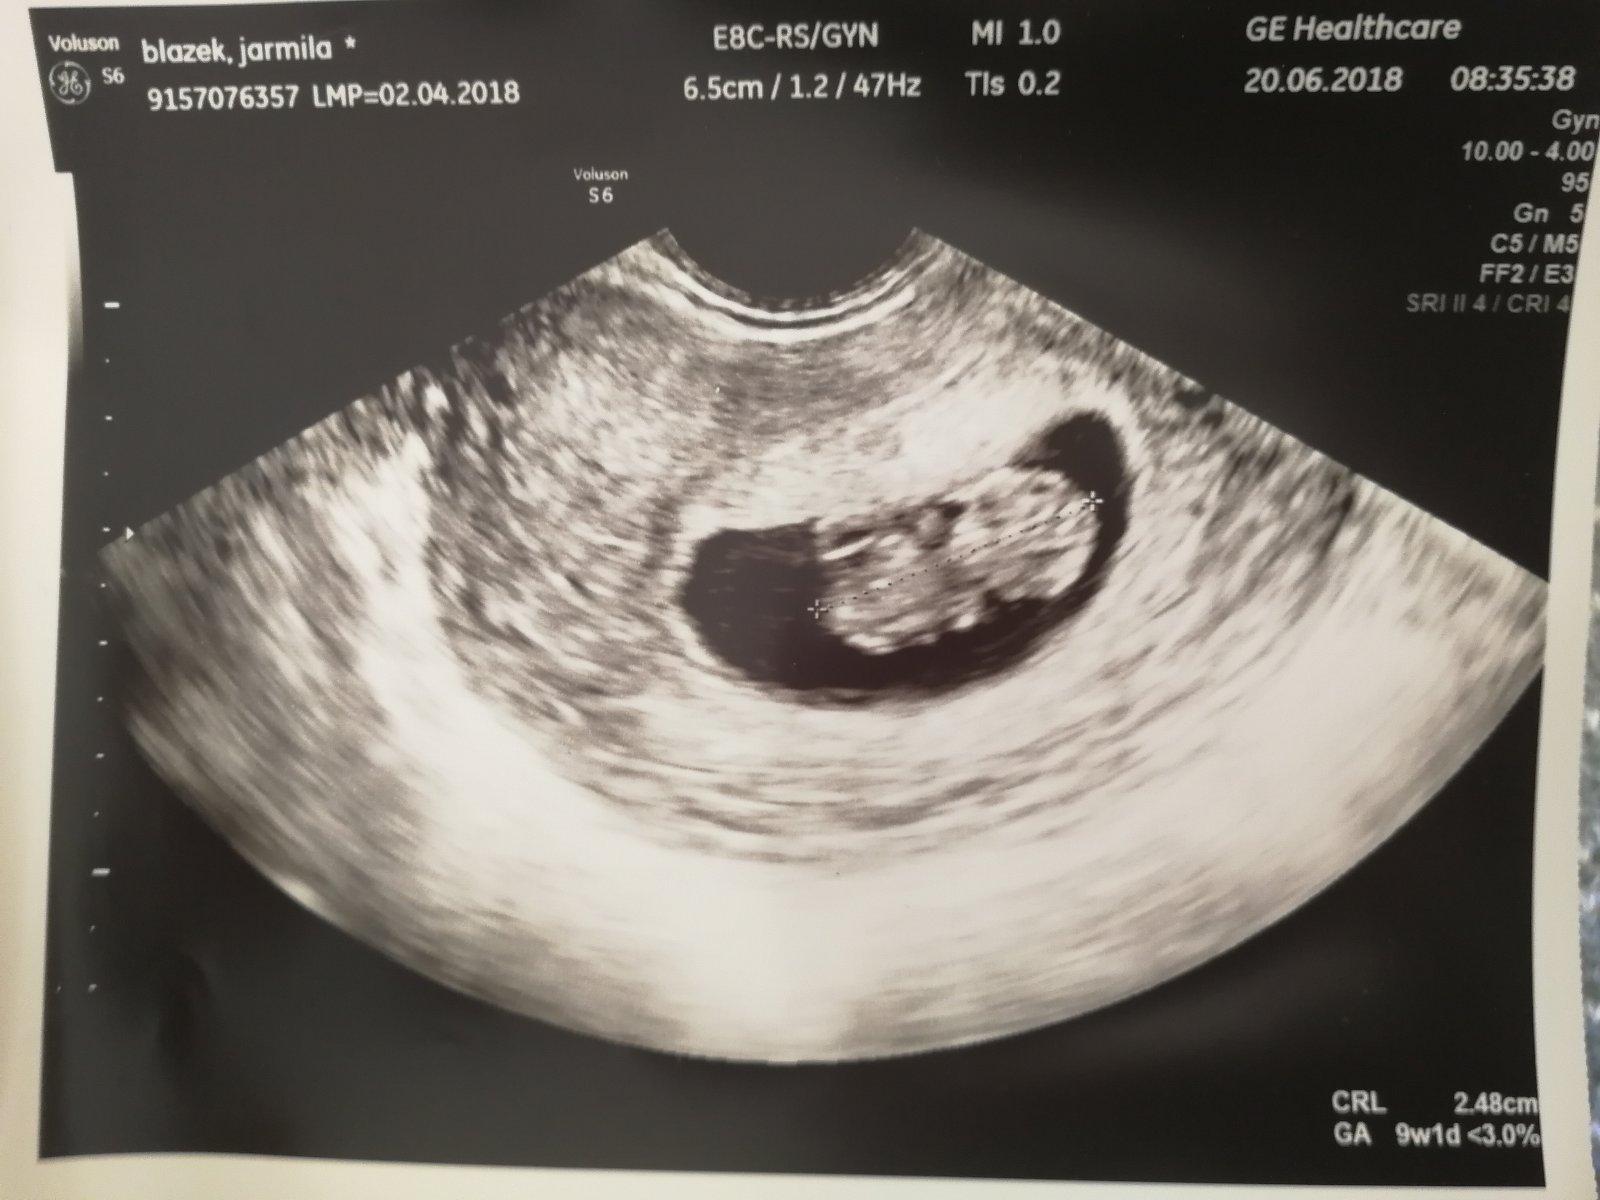

Babyyyyy srdiecko nam bije ako zvon a podrastli sme 😍😍